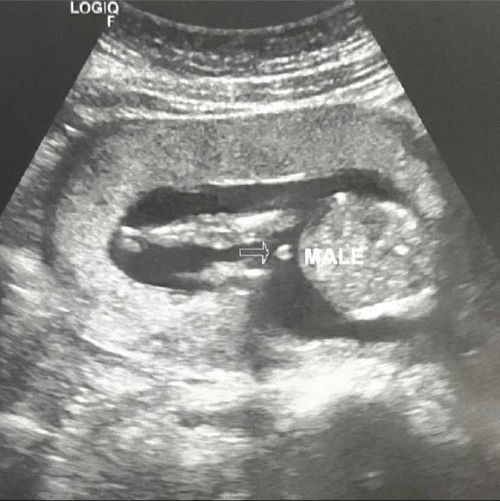

Hello mommies! This was my abdominal ultrasound at 16weeks featuring my baby boy. Patingin or papost naman sa baba ng gender ultrasound niyooo whether baby boy or gild. I would love to see it. ๐โค๏ธ๐ #boymom #firsttime_mommy #firstbaby #first_baby_16weeks